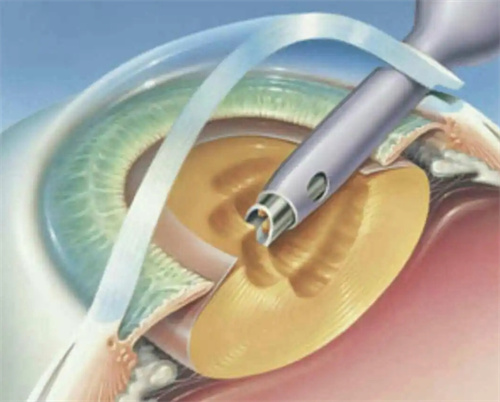

白内障手术是一种非常常见且安心的眼科手术,通常采用超声乳化技术将模糊的晶状体取出,然后植入人工晶状体以改善眼部视力。